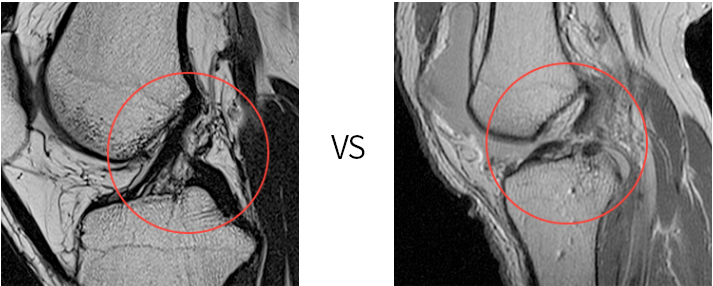

정상 전방십자인대(MRI)

파열된 전방십자인대(MRI)